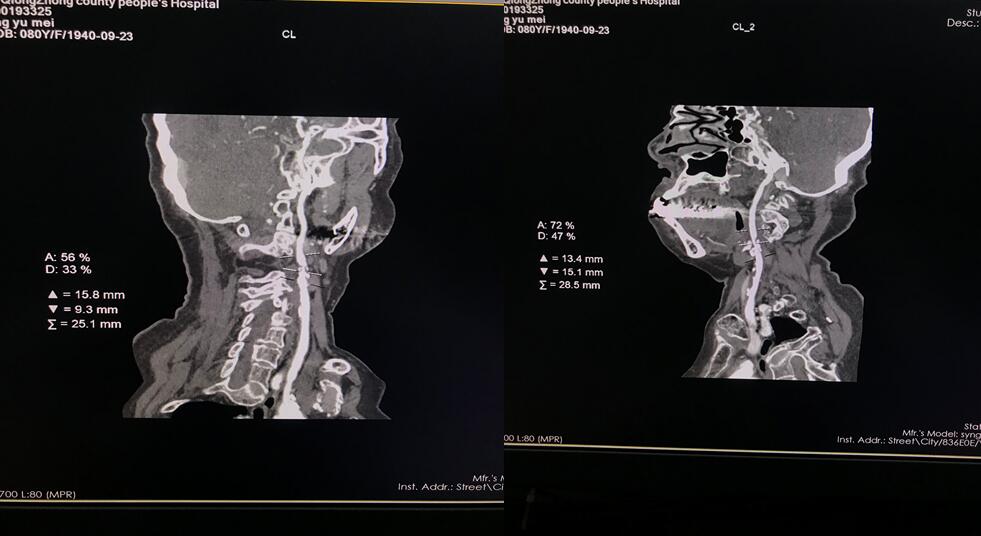

四、开展项目:科室现常规开展全身各部位CT平扫及增强检查、CT三维重建、CT血管造影(CTA、CTV)、(包括冠状动脉CTA)、CT尿路造影(CTU)、全身各部位DR摄片检查、床边摄片、同时开展胆系T管造影、CT定位下穿刺活检。

头颈CTA检查